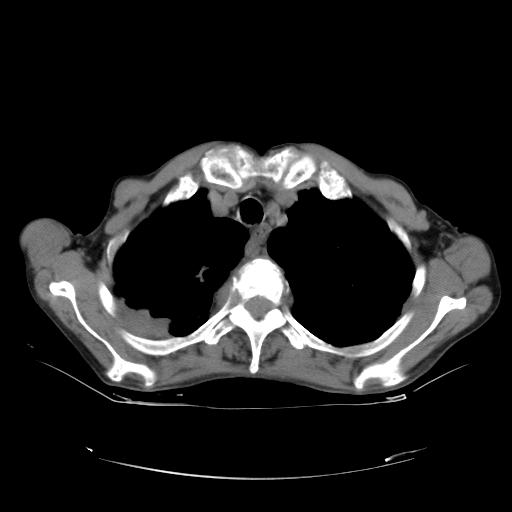

女,72岁,咳嗽一周余,突发右下肢无力二天。

pe:bp-140、80mmhg,精神可,伸舌居中,右上肢肌力正常,右下肢肌力0级,巴氏征+

来院做头颅+胸部ct平扫

本例颅内见多发大小不等高密度灶,有强化及水肿;另外,胸锁关节层面可能是第四胸椎及右侧肋骨起始部骨质欠连续,椎旁软组织肿胀,建议调骨窗观察。

右侧胸膜间皮瘤,双肺大泡,颅内多发转移(右顶叶、左侧侧脑室前角放射冠区)并出血。

左侧额叶及右顶叶实质内病灶首先应该考虑是转移性肿瘤伴出血{结合胸部强化}.